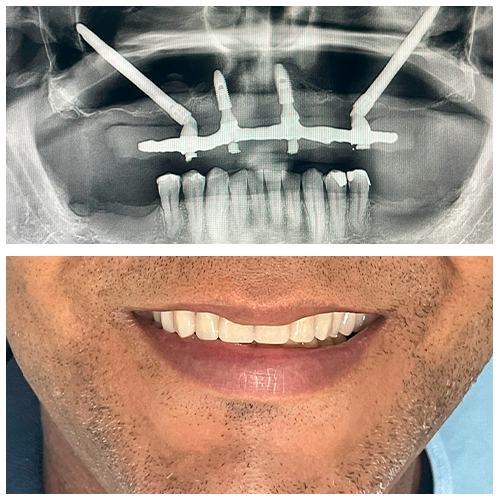

Com o implante zigomático, uma técnica avançada e segura, pacientes que antes não podiam fazer implantes tradicionais agora têm uma nova chance. Na Sorriso Feliz, contamos com profissionais experientes e tecnologia de ponta para transformar esse sonho em realidade — com confiança, cuidado e excelência.

Caso de implante zigomático realizado em nossa clínica.